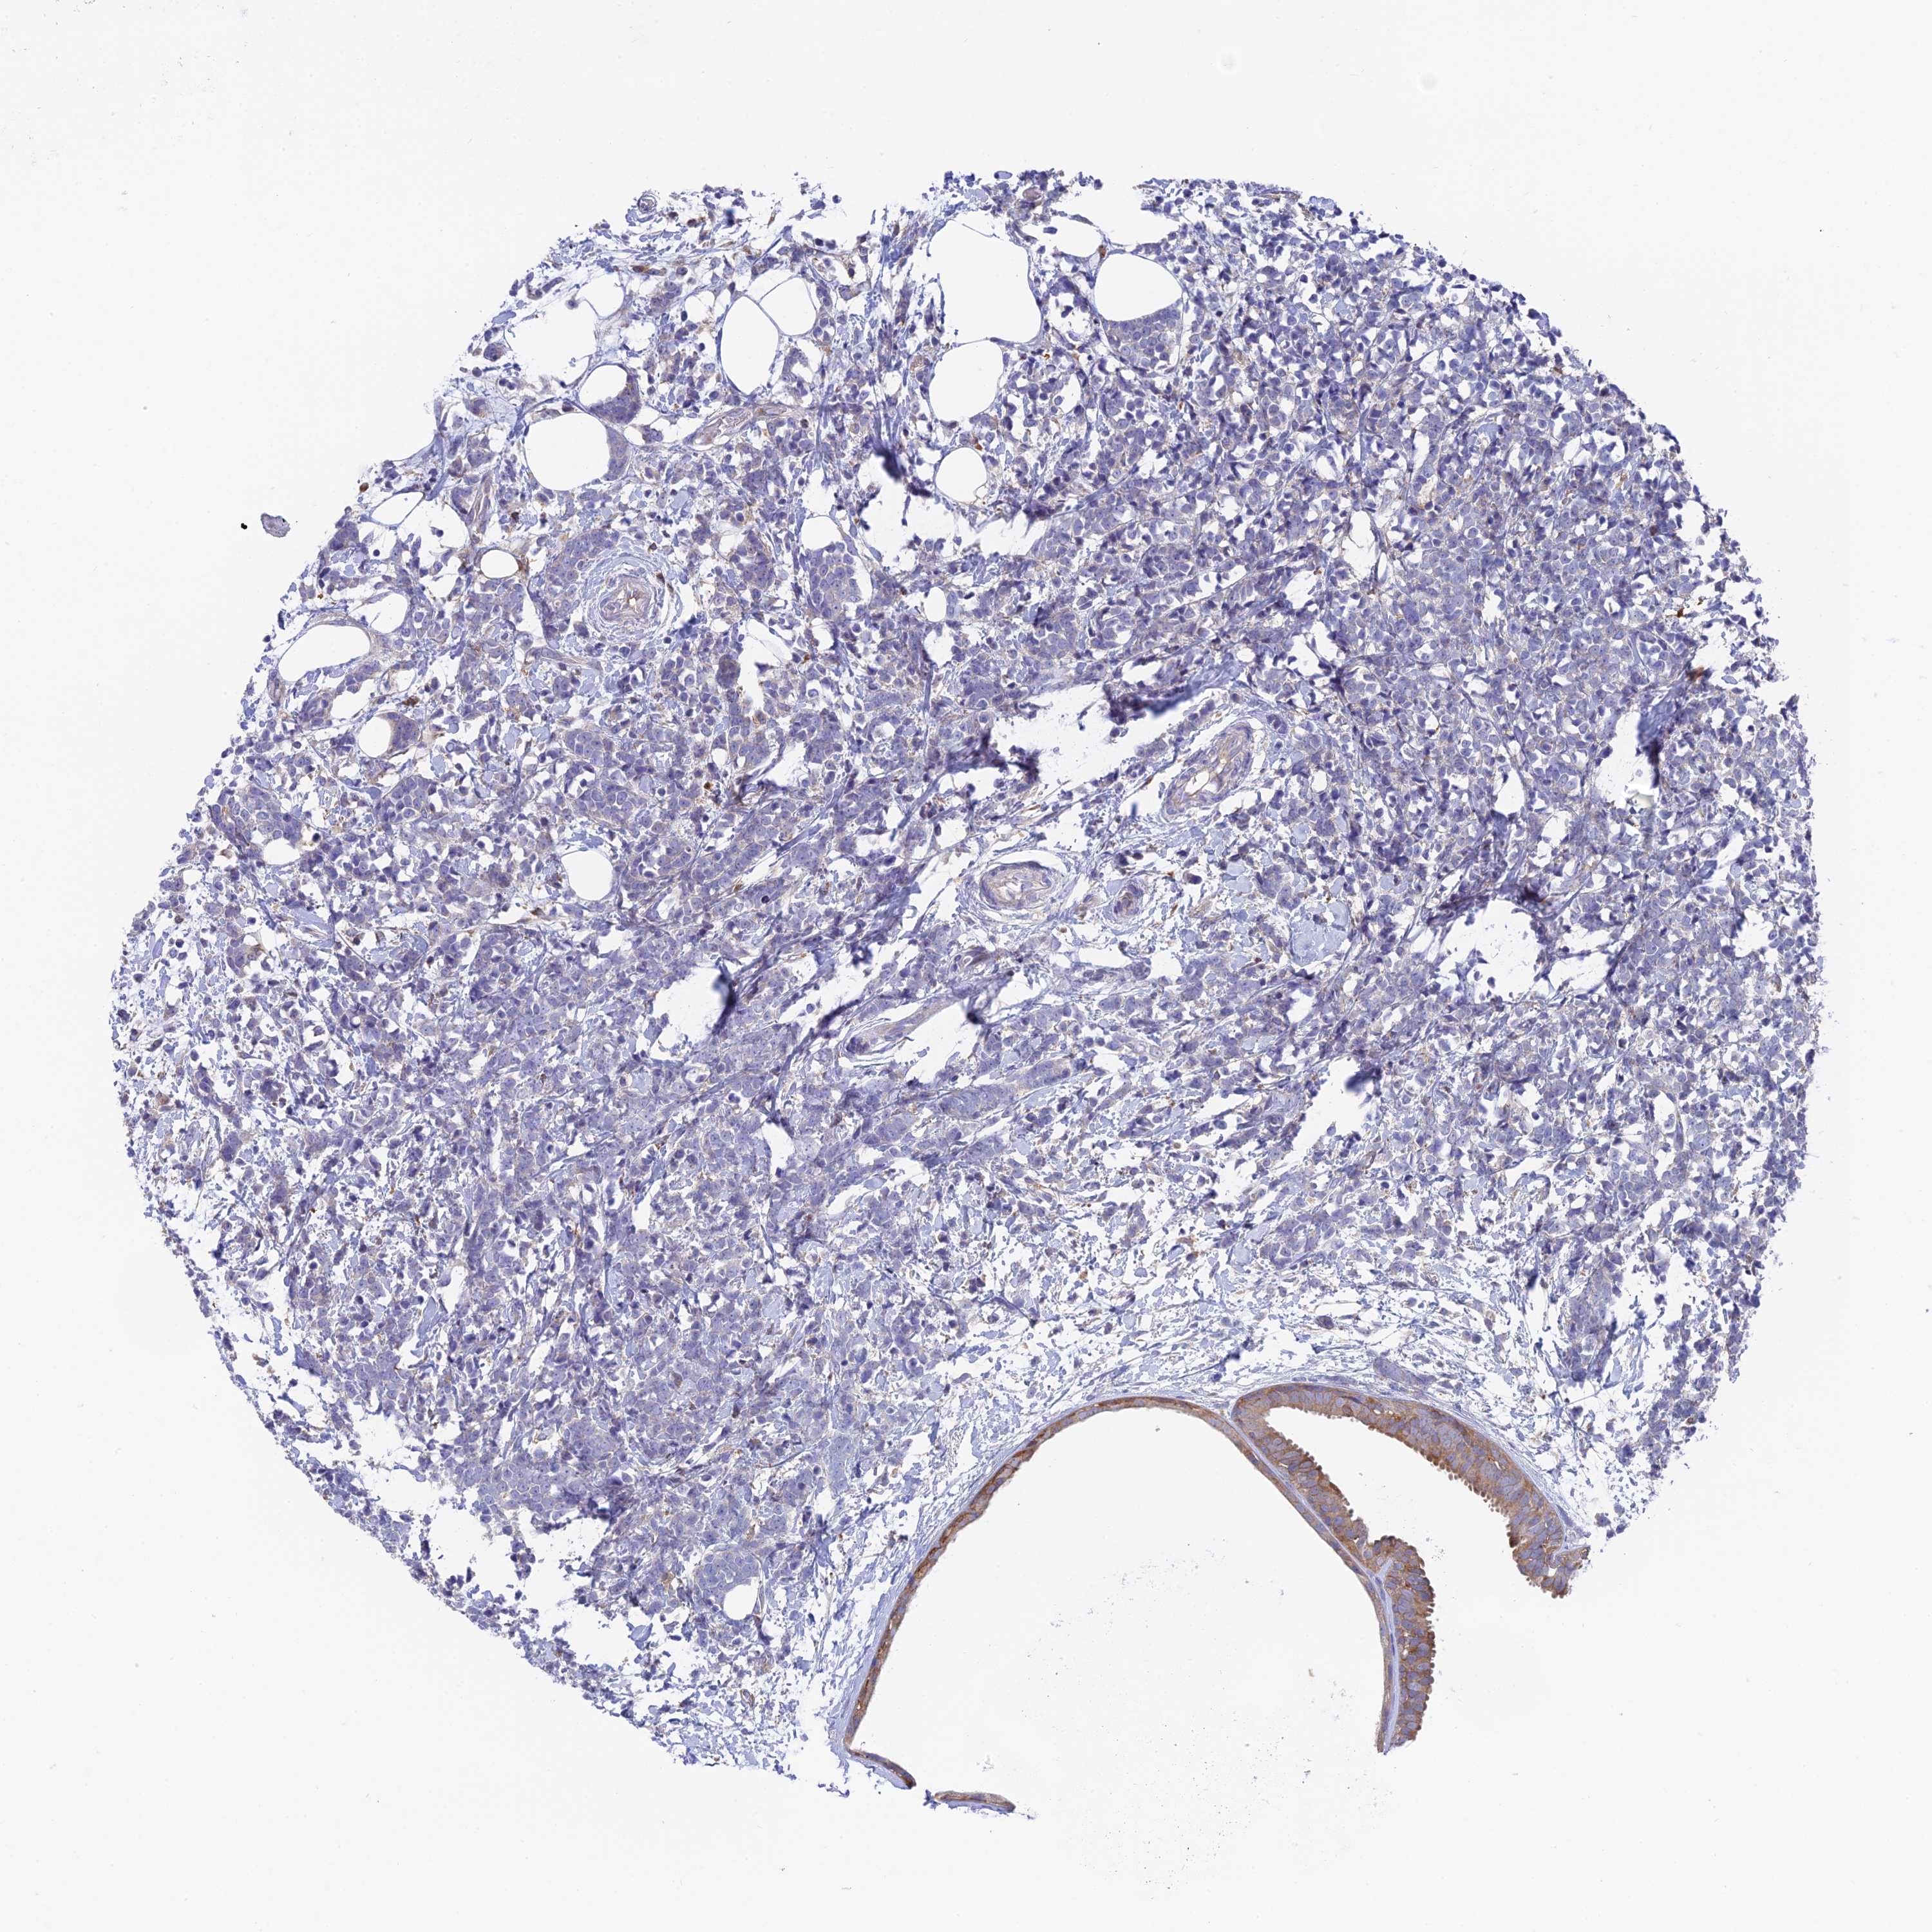

BRCA TCGA BRCA VALIDATION PROTEIN EXPRESSION